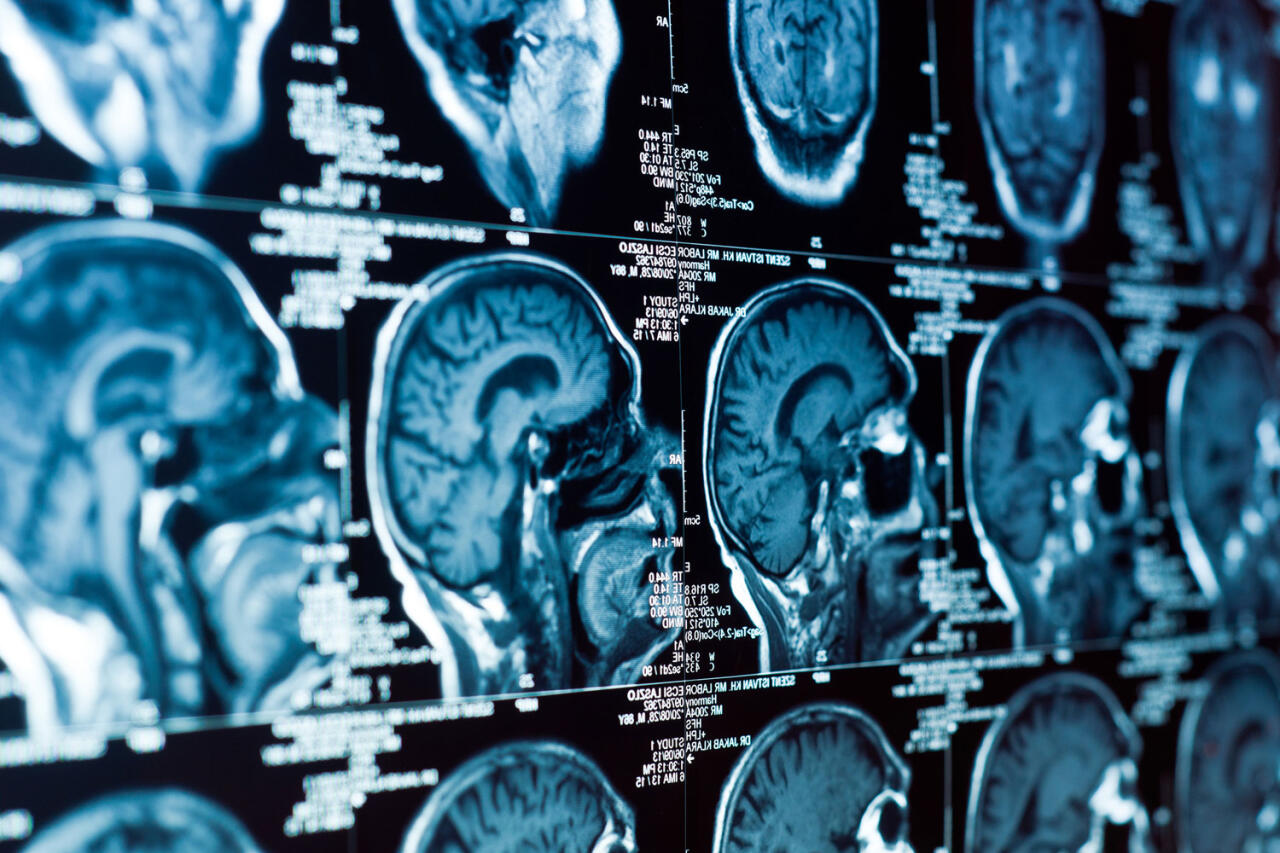

Найдена причина рецидива детского рака мозга

Ученые из исследовательского центра Sanford Burnham Prebys выяснили, что одной из причин рецидива нейробластомы - агрессивного рака мозга у детей - могут быть кольцевые внехромосомные элементы ДНК (вкДНК). Результаты работы опубликованы в журнале Cancer Discovery (CD), передает Day.Az со ссылкой на Gazeta.ru.